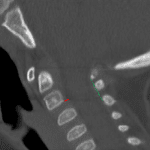

Age: 1

Sex: Male

Indication: Trauma

Case #14

Findings

- No acute fracture of the upper cervical spine (down to C3)

- Mild anterolisthesis of C2 on C3 without splaying of the posterior elements

- No prevertebral edema

Diagnosis

- No acute findings

- Pseudosubluxation

No acute fracture of the upper cervical spine (down to C3).

Mild anterolisthesis of C2 on C3 without splaying or offset of the posterior elements is favored to represent benign pseudosubluxation in this age group.

No prevertebral edema.